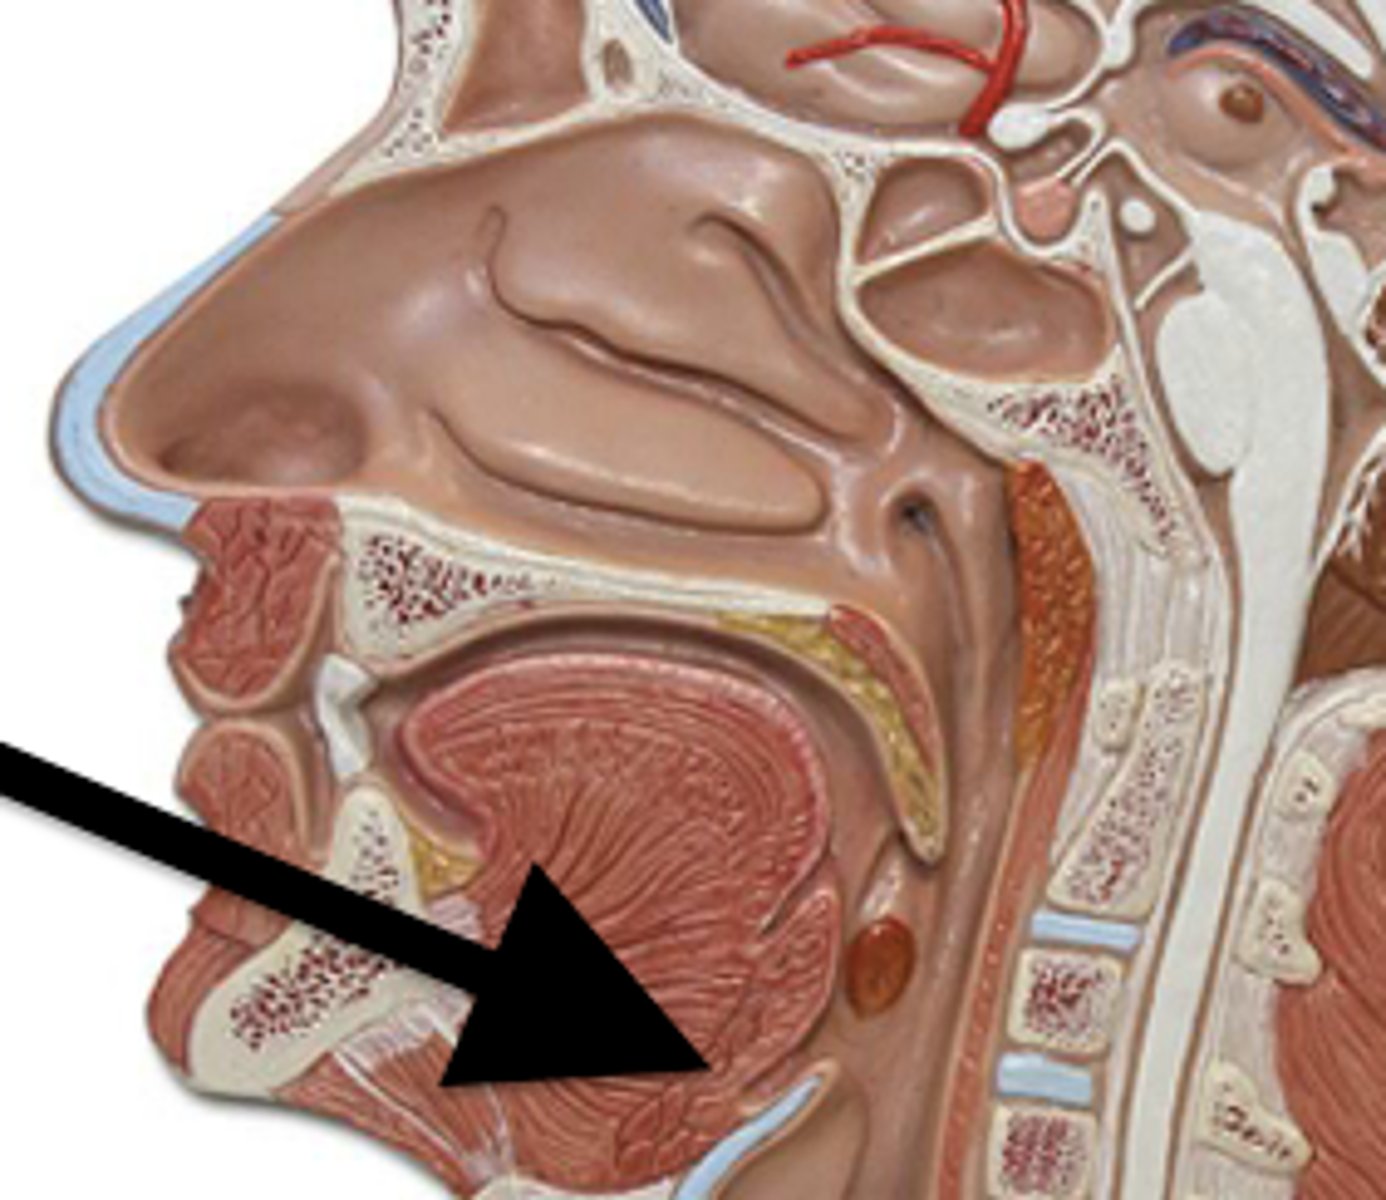

Oral Cavity

Mouth

Uvula

Soft tissue hanging from the middle of the soft palate

Salivary Glands

- Parotid

- Submandibular

- Sublingual

Parotid Gland

Salivary gland within the cheek, just anterior to the ear (red)

Submadibular Gland

Salivary gland under the mandible (green)

Sublingual Gland

Salivary gland under the tongue (yellow)

Functions of the Mouth

- First part of the digestive system

- Formation of speech

- Sense of taste

Pharynx (Throat)

Passageway for air, leads to trachea

Function of Throat

- Passageway for food

- Passageway for air

- Tonsils are part of the immune system

Tonsils

Masses of lymphatic tissue in the back of the oropharynx

3 Tonsils in the Mouth

- Palatine

- Adenoid

- Lingual

Palatine Tonsil

One of a pair of almond-shaped masses of lymphatic tissue in the oropharynx

Adenoid Tonsil

Pharyngeal tonsil

Lingual Tonsil

Tonsil located at the base of tongue